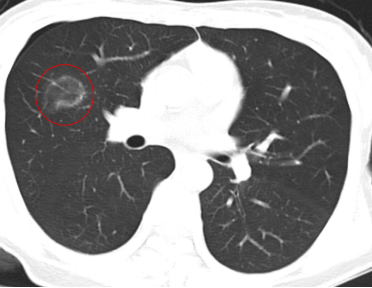

位置特殊,术前精密规划穿刺路线

介入治疗科团队在王女士入院后认真评估患者病情,考虑到患者肺磨玻璃结节位于右肺叶间裂附近,且病灶周围血管较多,术中容易引起气胸、出血等并发症。

图片

图中黄色箭头为术前模拟规划的穿刺路线

医疗组在术前的CT图像上多角度反复模拟穿刺,经过科室讨论后最终确定了理想的穿刺进针路线,为手术提供了参考方案。